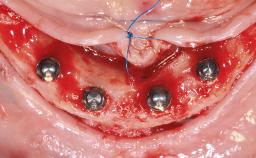

Treatment of a Fractured Edentulous Mandible Following Extraction of All Residual Teeth Using Computer-Guided Surgery and Immediate Loading

A 65-year-old female patient was referred to our clinic by another patient for evaluation and treatment of her compromised dental clinical situation. The patient presented with a pessimistic attitude and declared she had no confidence in the possibility of improving her oral situation. Her main complaint was discomfort, inability to chew, and collapse of the facial tissues related to her medical history. The patient had a serious domestic accident 18 months before the consultation and suffered from a head injury, followed by 4 months in a coma. She then gradually progressed toward almost complete neurological recovery, although, at the time of the consultation, she still had difficulty walking. The patient suffered a mandibular fracture in that accident, but because her life had been in danger, the fracture had been ignored. Since the patient was immobilized at the hospital for 4 months, the mandibular fracture had healed spontaneously, but the fragments reossified in an incorrect position, which resulted in a complete discrepancy between the positions of the remaining mandibular teeth and the maxillary teeth